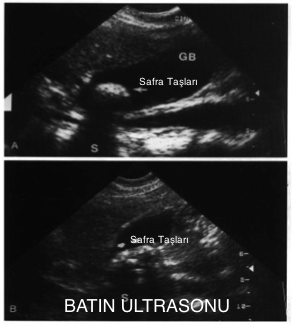

Tanıda kullanılan en güvenilir yöntem batın ultrasonudur. Gerekli hallerde batın tomografisi de kullanılabilir.